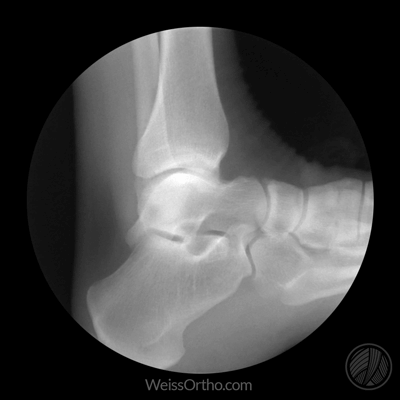

Met X-rays of Röntgenstralen kunnen we in ons lichaam kijken, maar we kennen het meestal gewoon als een foto: een stilstaand beeld van botten of gewrichten. Door fluoroscopie kunnen echter ook bewegende beelden gemaakt worden.

Ontwerper en fotograaf Cameron Drake ging aan de slag met beelden van het orthopedisch instituut van Dr. Noah Weiss in de V.S. (Weis Orthopaedics). Op zijn blog legt Drake uit hoe hij de beelden die Dr. Weiss gemaakt heeft van zijn patiënten omgezet heeft in deze gifs.